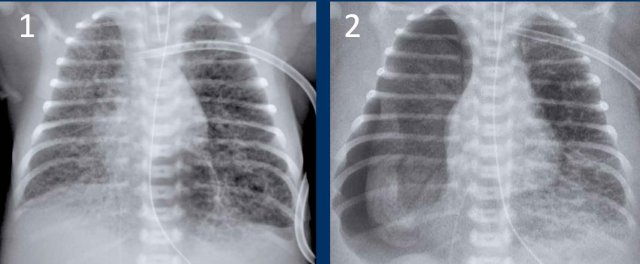

Premature of 25 weeks and 5 days, now 2 month old. Treatement for RDS

1. The first chest radiograph shows hyperinflation, and a markedly enlarged heart with increased vascular markings and interstitial markings.

NG tube and duodenal tube in situ.

2. After 5 days of treatment there is less hyperinflation and normalization of the heart size and vascular markings.

There still remain some interstitial markings, in keeping with BPD.